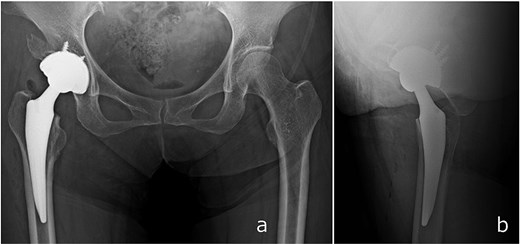

Full weight-bearing was allowed from postoperative day 1. The patient regained independent ambulation and was discharged home on postoperative day 28. At 6 months, she had resumed recreational activities with a Harris Hip Score of 92. No complications were observed, and follow-up CT demonstrated healing of the anterior wall fracture and partial union of the AIIS fragment (Fig. 5).

Radiographs (a and b) and CT images (c and d) obtained at 6 months postoperatively, showing stable implant fixation and partial union of the anterior inferior iliac spine and acetabular anterior wall fractures.